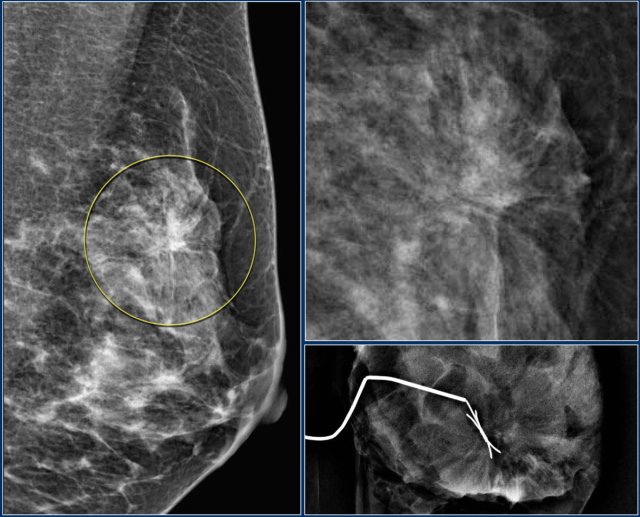

Notice the distortion of the normal breast architecture on oblique view (yellow circle) and magnification view.

A resection was performed and only scar tissue was found in the specimen.